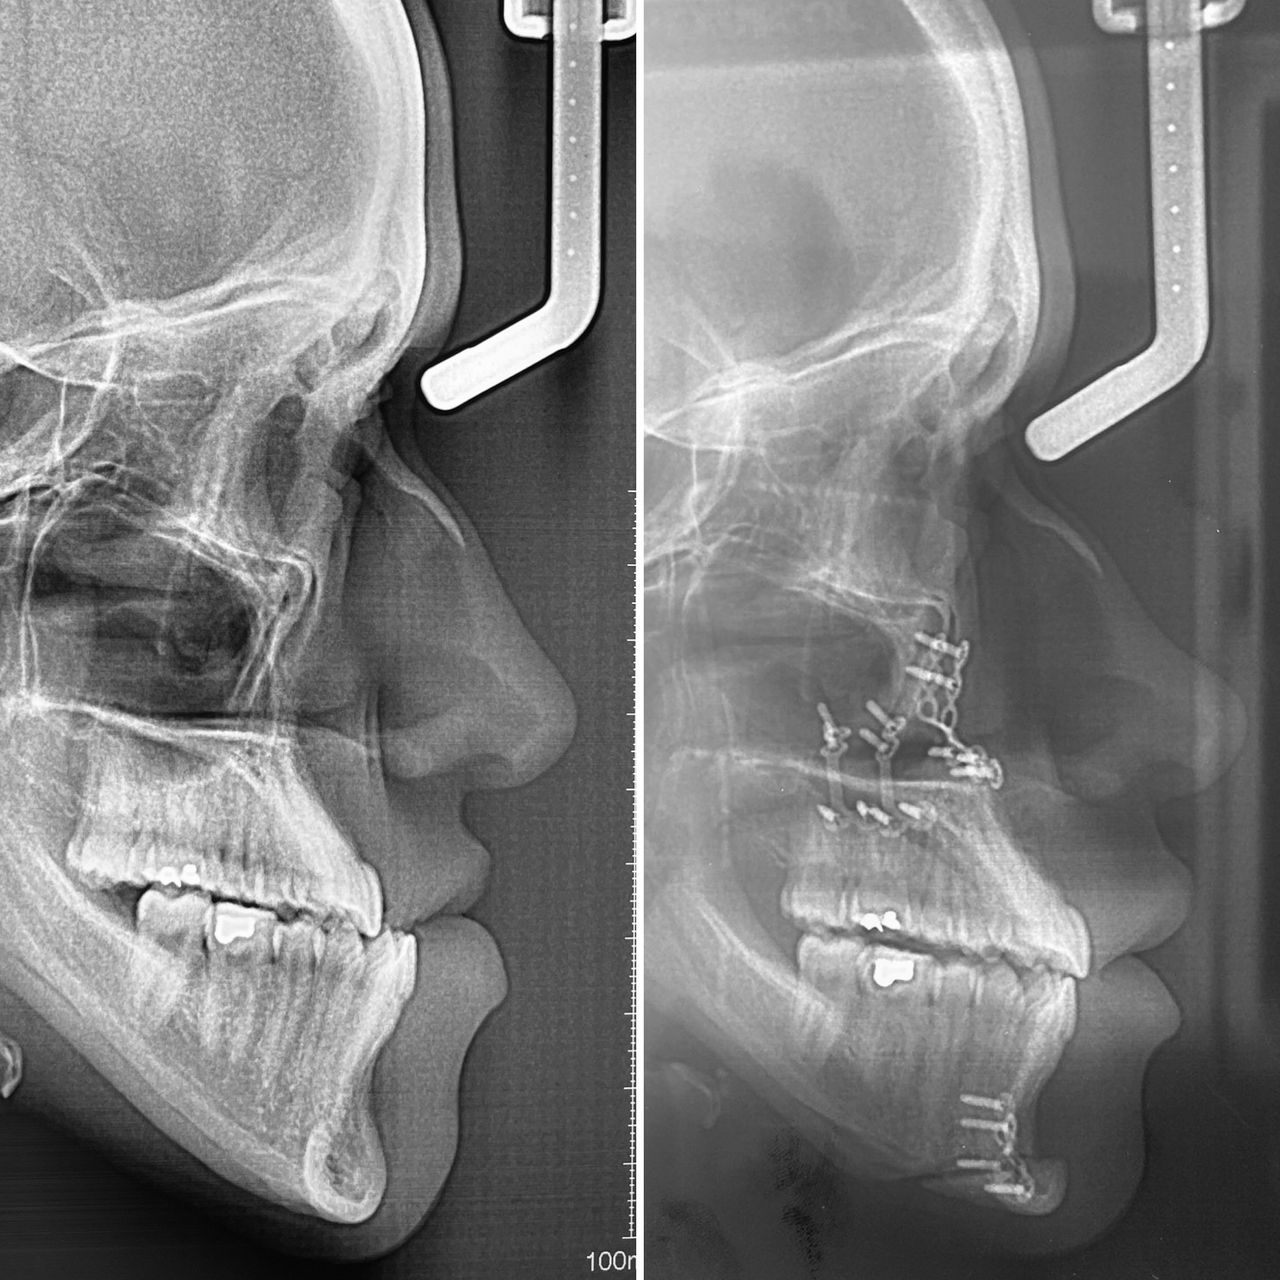

En el área de cirugía maxilofacial tengo experiencia en el manejo quirúrgico de trauma facial, anomalías dento-faciales, disfunción de articulación temporomandibular, reconstrucción de maxilares, Cirugía estetica Facial, blefaroplastia, otoplastia, mentoplastia, Lifting facial, Lip Lift y reposicionamiento labial, retiro de biopolimeros en cara y Armonización Oro-Facial.

In the field of maxillofacial surgery, I have experience in the surgical management of facial trauma, dentofacial anomalies, temporomandibular joint dysfunction, mandibular reconstruction, facial cosmetic surgery, blepharoplasty, otoplasty, mentoplasty, facelifts, lip lifts and lip repositioning, removal of facial biopolymers, and orofacial harmonization.

- Cirugía ortognática